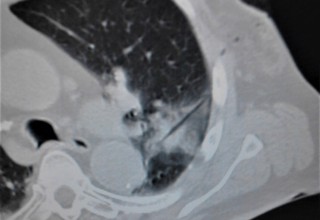

Lung tumor receiving microwave ablation treatment

Doctors at National Taiwan University are successfully using microwave energy to minimally invasively treat tumors in the lung with higher local success rate of 84 percent compared to historical 67-78 percent.

The doctors apply microwave energy to destroy tumors located both centrally and peripherally within the lung using computer tomography (CT) image guidance. The tumors include colorectal cancer, lung adenocarcinoma, thymoma, uterine leiomyosarcoma and ampullary carcinoma in origination. Microwave energy applicators are introduced into the tumors in the lung percutaneously, a minimally invasive technique. A small hole is made through the skin near the tumor location and an applicator is inserted into the lung cavity and lung towards the tumor. Once the positioning of the antenna with respect to the tumor is verified with CT image guidance, microwave energy is applied to the antenna in contact with the tumor to destroy it. The procedures usually take an hour or two depending on the complexity of tumor location and shape to achieve good antenna positioning. The microwave energy application is controlled with direct temperature feedback from the ablation antenna during the procedure to ensure safety and efficacy. Temperature feedback control prevents overheating and runaway conditions and thereby provides the extra safety net for the patients and procedures.